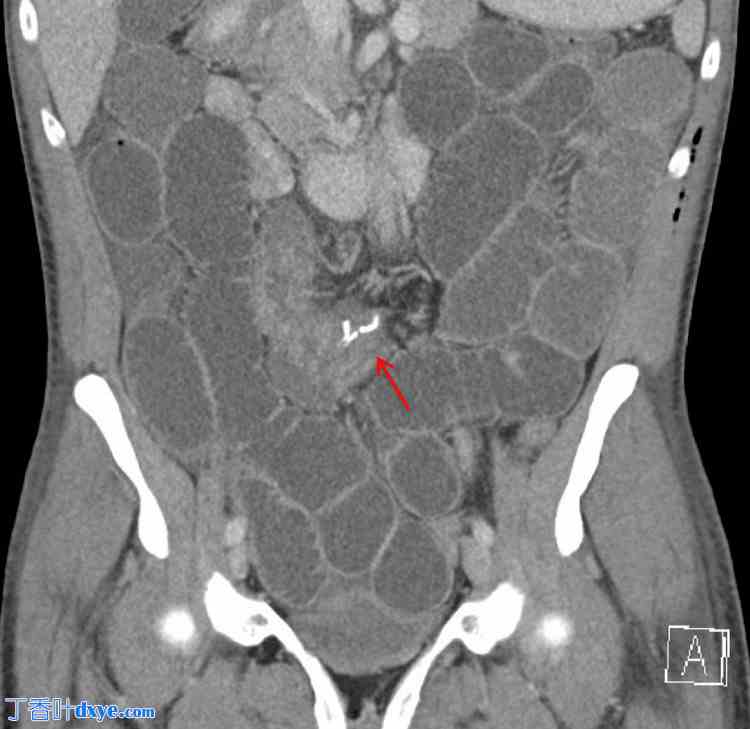

术后第二天,患者出现恶心、呕吐和腹胀。CT 扫描显示腹部中央、肠系膜内、手术吻合口近端存在小肠闭环梗阻(图 2、3)。这提示可能存在内疝或其他术后并发症。

图 3. 腹部及盆腔增强 CT(轴向位)显示小肠闭式梗阻(红色箭头),位于腹部中部肠系膜,靠近手术吻合口。